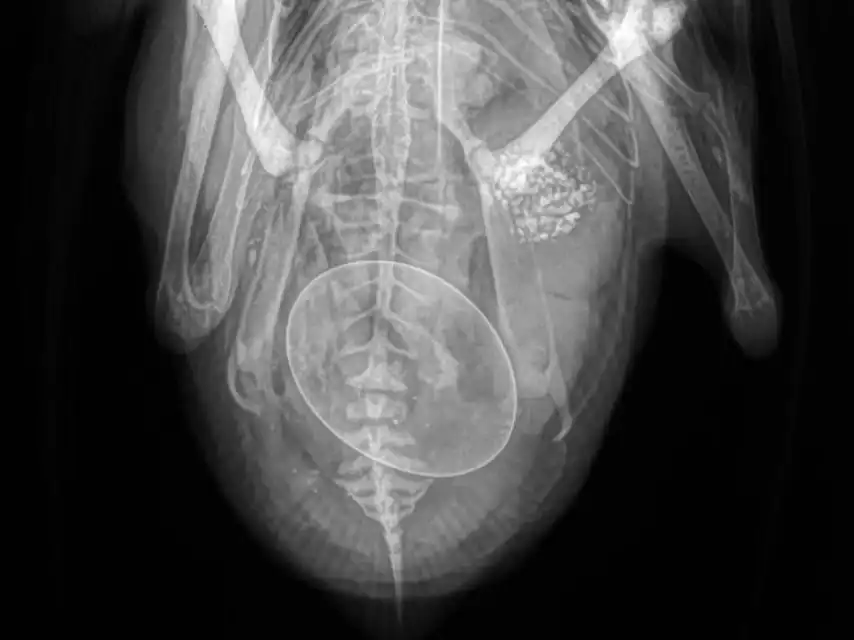

The vet carefully examined our duck and took X-rays. The latter revealed that she indeed had an egg stuck inside her. It was sideways, which is why she had so much trouble getting it out.